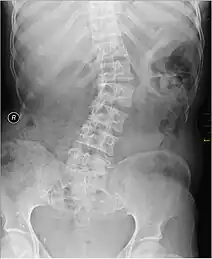

| Kyphosis (left) and scoliosis (right) depicting iliocostal contact (a) | |